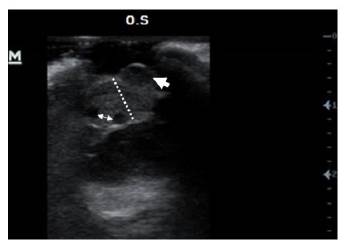

Se realizó ecografía ocular con transductor lineal de 14 MHz para evaluar extensión de la lesión, se apreció engrosamiento iridal severo en región ventrolateral del mismo con presencia de una masa adherida (no medida) con una porción hipoecoica hacia anterior y dos porciones anecoicas hacia posterior de la lesión (Figura 4), la ecogenicidad de la cámara anterior, cámara posterior y cámara vítrea se encontró conservada, la posición y ecogenicidad del lente se encontraron adecuadas, la túnica posterior estaba posicionada adecuadamente (Figura 5).